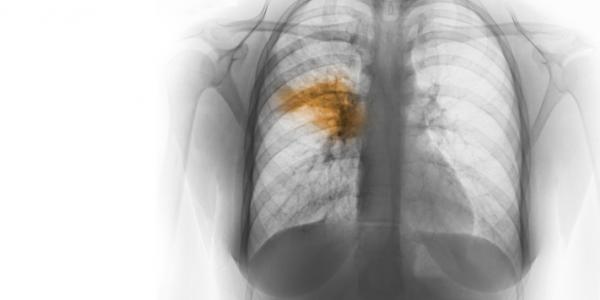

Pneumonia është një infeksion i njërës ose të dy mushkërive, të cilat mbushen me lëng dhe qelb, duke e bërë frymëmarrjen veçanërisht të vështirë.